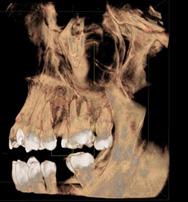

Protocolo Odontológico Quirúrgico Aplicado a Pacientes con VIH+: A propósito de un caso clínico

Reporte de Caso

Surgical Dental Protocol Applied to Patients with HIV

+: About a clinical case

Javier Boris Adrián Burgos

Nathalie Andrea Candia López

Noelia Vargas Ovando